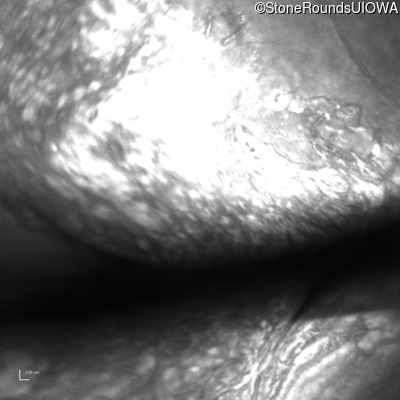

B-Scan Ultrasonography - Right - 20/200 sc

Exemplar